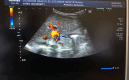

Diagnoses: Physical examination revealed jaundice and hepatosplenomegaly. Abdominal ultrasonography identified hepatosplenomegaly, mild ascites, and portal cavernoma. A liver biopsy confirmed a diagnosis of EHBA.